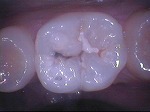

◆コンポジット充填

~修復前~

コンポジットレジン充填

~修復中~

~修復後~

~臼歯術前~

~臼歯術後~